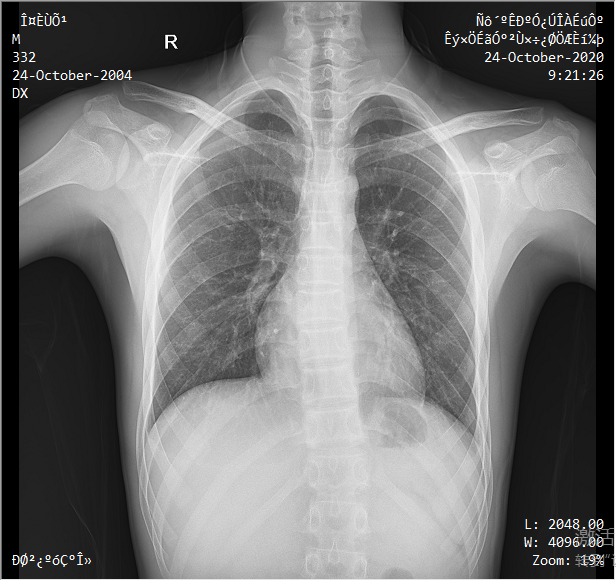

采用靈活的懸吊式機(jī)架設(shè)計,配置電動升降攝影床/移動床與高品質(zhì)平板探測器,實現(xiàn)圖像與擺位的有機(jī)統(tǒng)一,可應(yīng)用于DR攝影多種臨床X線檢查領(lǐng)域。

醫(yī)生選擇需要拍攝的部位,自動生成擺位示意圖像,引導(dǎo)病人快速準(zhǔn)確的完成擺位。

依據(jù)臨床圖像庫自動進(jìn)行圖像后處理,呈現(xiàn)效果佳。